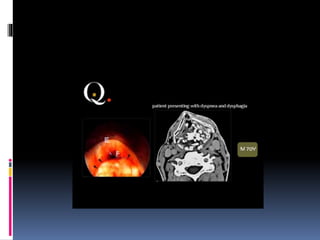

IMAGING OF THE PHARYNX

IMAGING OF LARYNX